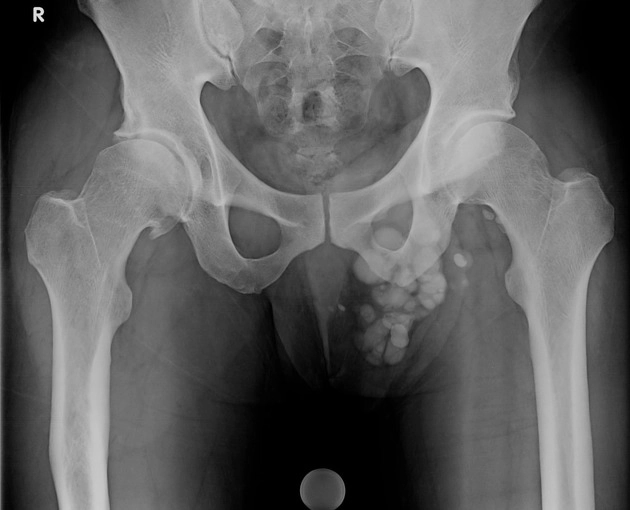

Sỏi bìu (Scrotolith)

16/03/2026